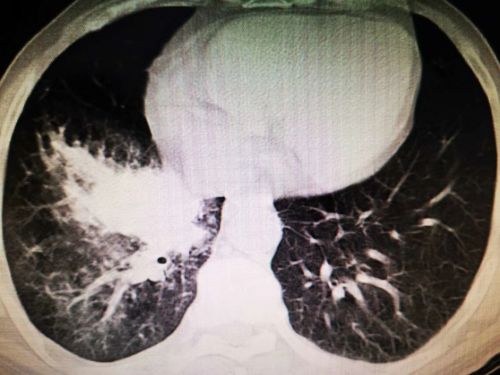

6月上旬,湖南宁乡75岁的姜爷爷连续4天发高烧,最高体温达到40.1℃,可自行退烧,除阵发性腹痛外没有其他不适。无规律的高热让平时身体硬朗的老人没了精气神,吃了几天中药不见好转,在家人的反复劝说下,来到湖南省人民医院就诊。初步筛查排除新冠肺炎后,老年医学中心何翠娥副主任医师仔细询问病史,并为其进行详细的体格检查, CT 检查提示:1.右下肺阻塞性肺炎;2.右下肺团块灶,性质待定,考虑肿瘤可能性大。随即将其收入老年医学中心二病室,做进一步的检查和治疗。

入院后,何翠娥副主任医师、谌彦副主任医师组织病情讨论。何医师凭借多年临床经验判断,不排除进食呛咳等导致吸入性肺炎的可能性,于是反复向老人和家属询问是否有进食呛咳史,均予以否认,表示没有咳嗽、咯血等症状。

呼吸与危重症医学科吴怀球副主任医师为老人进行支气管纤维镜检查,从其右下叶基底段支气管内取出2颗果核,经家属辨认为桂圆核。据姜爷爷的老伴回忆,今年春节后很长一段时间,因疫情原因不能串门,姜爷爷吃完晚饭就会斜躺在床上看电视,有时还边看电视边吃零食,桂圆核估计就是那时候误入气道的。